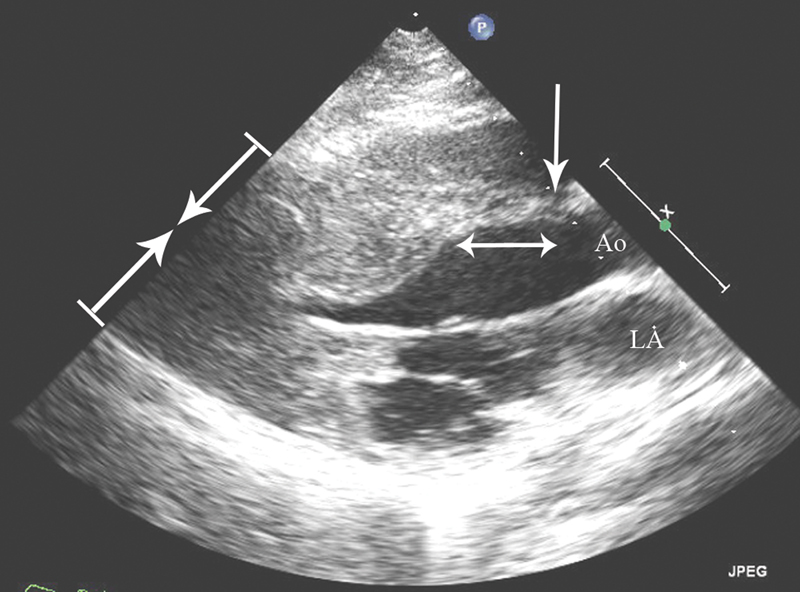

فحوصات تشخيصية لبعض امراض القلب والشرايين التاجية